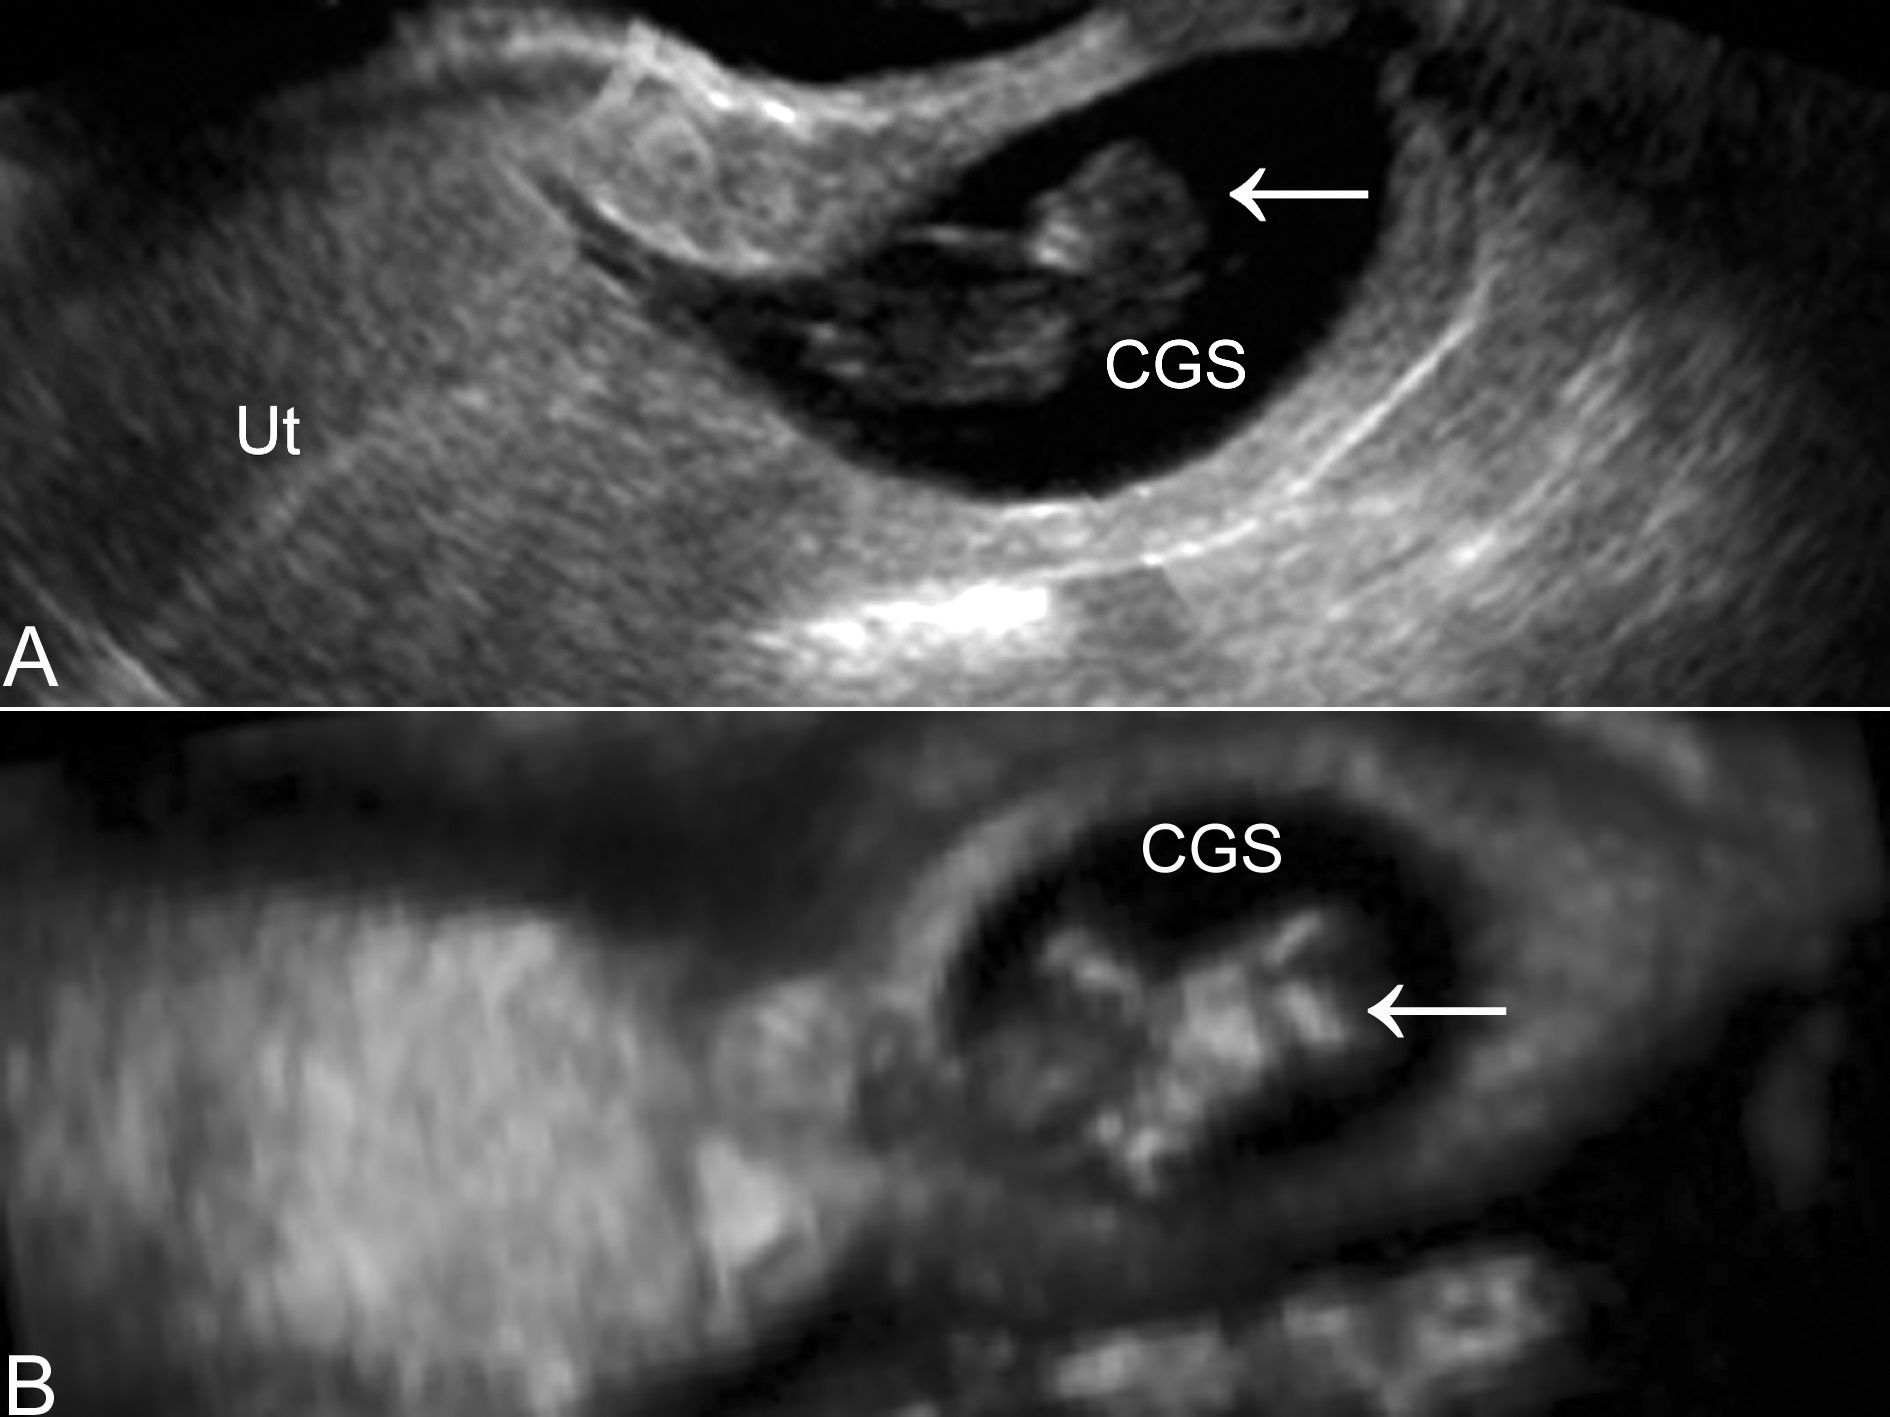

超声显像检查在子宫颈内发现妊娠征象,并不一定都是子宫颈妊娠,也可能是子宫腔妊娠流产移至子宫颈或子宫瘢痕处妊娠所致。单纯以超声显像检查显示包块的回声难以做出鉴别诊断。超声显像检查显示不规则的异常回声,与子宫颈分界清楚,病人出现腹痛后出现阴道流血,出血量也比较少,超声多普勒彩色血流显像检查在妊娠团块中不能发现血流时,一般提示为子宫腔妊娠流产;子宫颈管可以显示,妊娠团块位于子宫前下壁,局部不能显示正常的子宫肌层或在妊娠团块与膀胱之间缺少子宫肌层回声,结合病人的剖宫产史应考虑有子宫瘢痕处妊娠可能。经阴道检查是有诱发阴道出血之虑;三维超声检查可以对子宫颈进行冠状面等多切面的重建显示,有利于宫颈妊娠的显示(图2)和鉴别诊断。

图2子宫颈妊娠声象图(A)及三维显示(B)